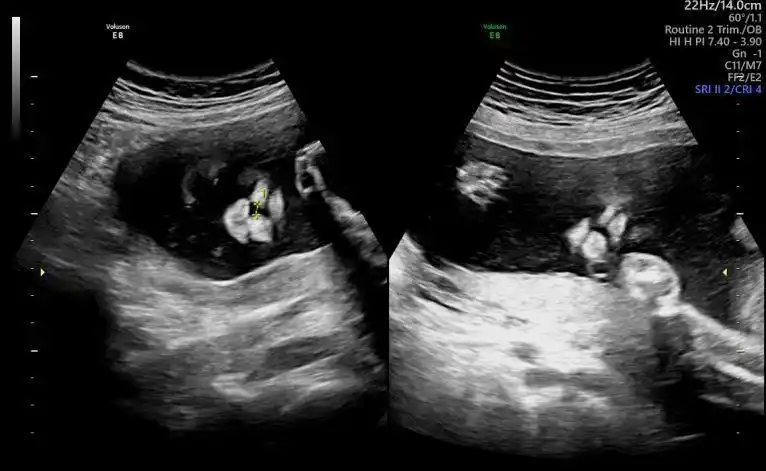

双胎宝妈21周做四维彩超筛查出一名胎儿为唇腭裂

双胎宝妈21周做四维彩超,筛查出一名胎儿为"唇腭裂"